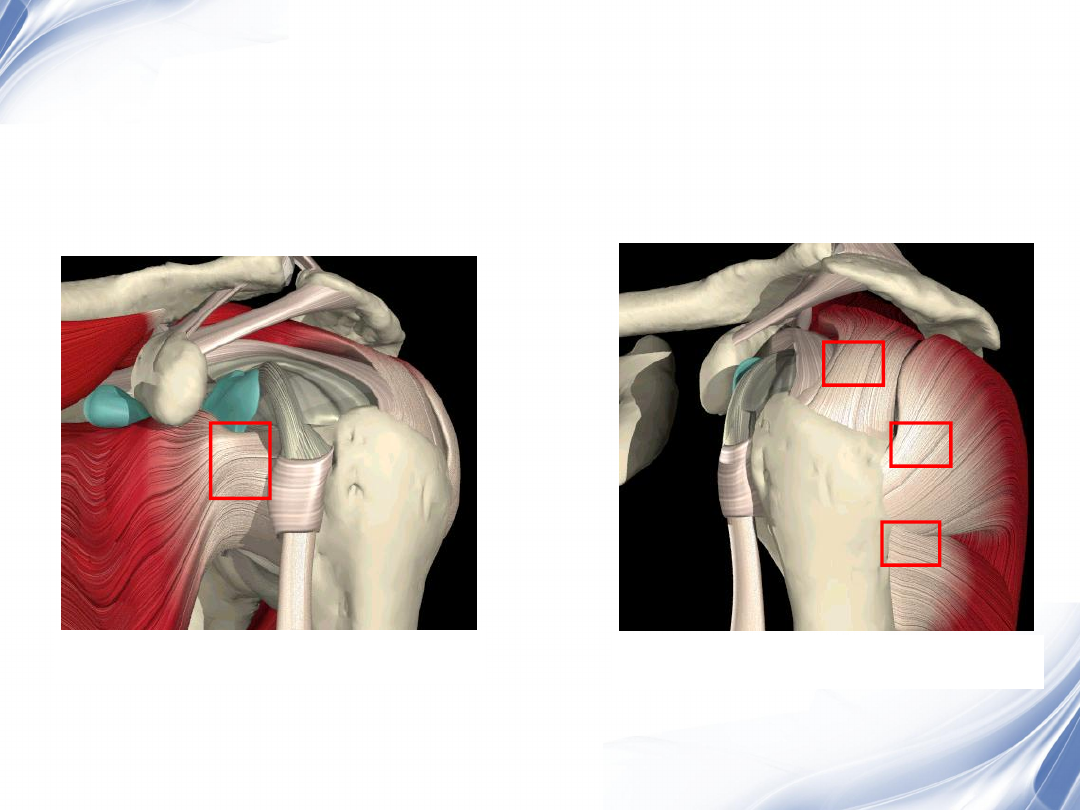

肩袖的解剖

冈上肌肌腱

冈下肌肌腱

小圆肌肌腱

肩胛下肌肌腱

肩袖损伤病理分级

Neer

将肩袖的慢性改变的病理过程分为三级:

•I

级

肌腱炎

肌腱的水肿和出血,尤其是冈上肌腱

•II

肌腱退变和纤维化(包括肩袖部分撕裂)

•III

肩袖全层撕裂